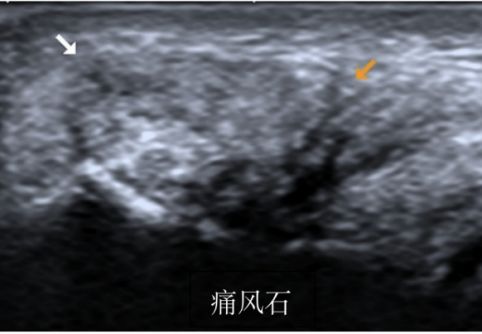

所谓肌肉骨骼系统超声,简称“肌骨超声”,就是常规超声诊断设备通过专用高频超声探头对人体肌肉、软组织及骨骼病变等疾病进行明确诊断的超声检查方法。

相比传统的检查方法,如X线、CT、MRI(核磁共振)等,“肌骨超声”除具有无创、无辐射、无禁忌症、廉价等诸多优势之外,还具有能够对肌肉、肌腱的运动进行实时动态观察的独特优势,尤其是高频超声探头的应用,细微分辨率的显著提高,能清晰显示肌肉、肌腱、韧带、神经等组织病变,可以和CT、MRI媲美并互补,甚至可以提供其他影像学检查无法得到的重要诊断信息。

创伤性关节炎、痛风性关节炎、类风湿性关节炎、感染性关节炎、退行性骨关节病、各种滑囊炎等。